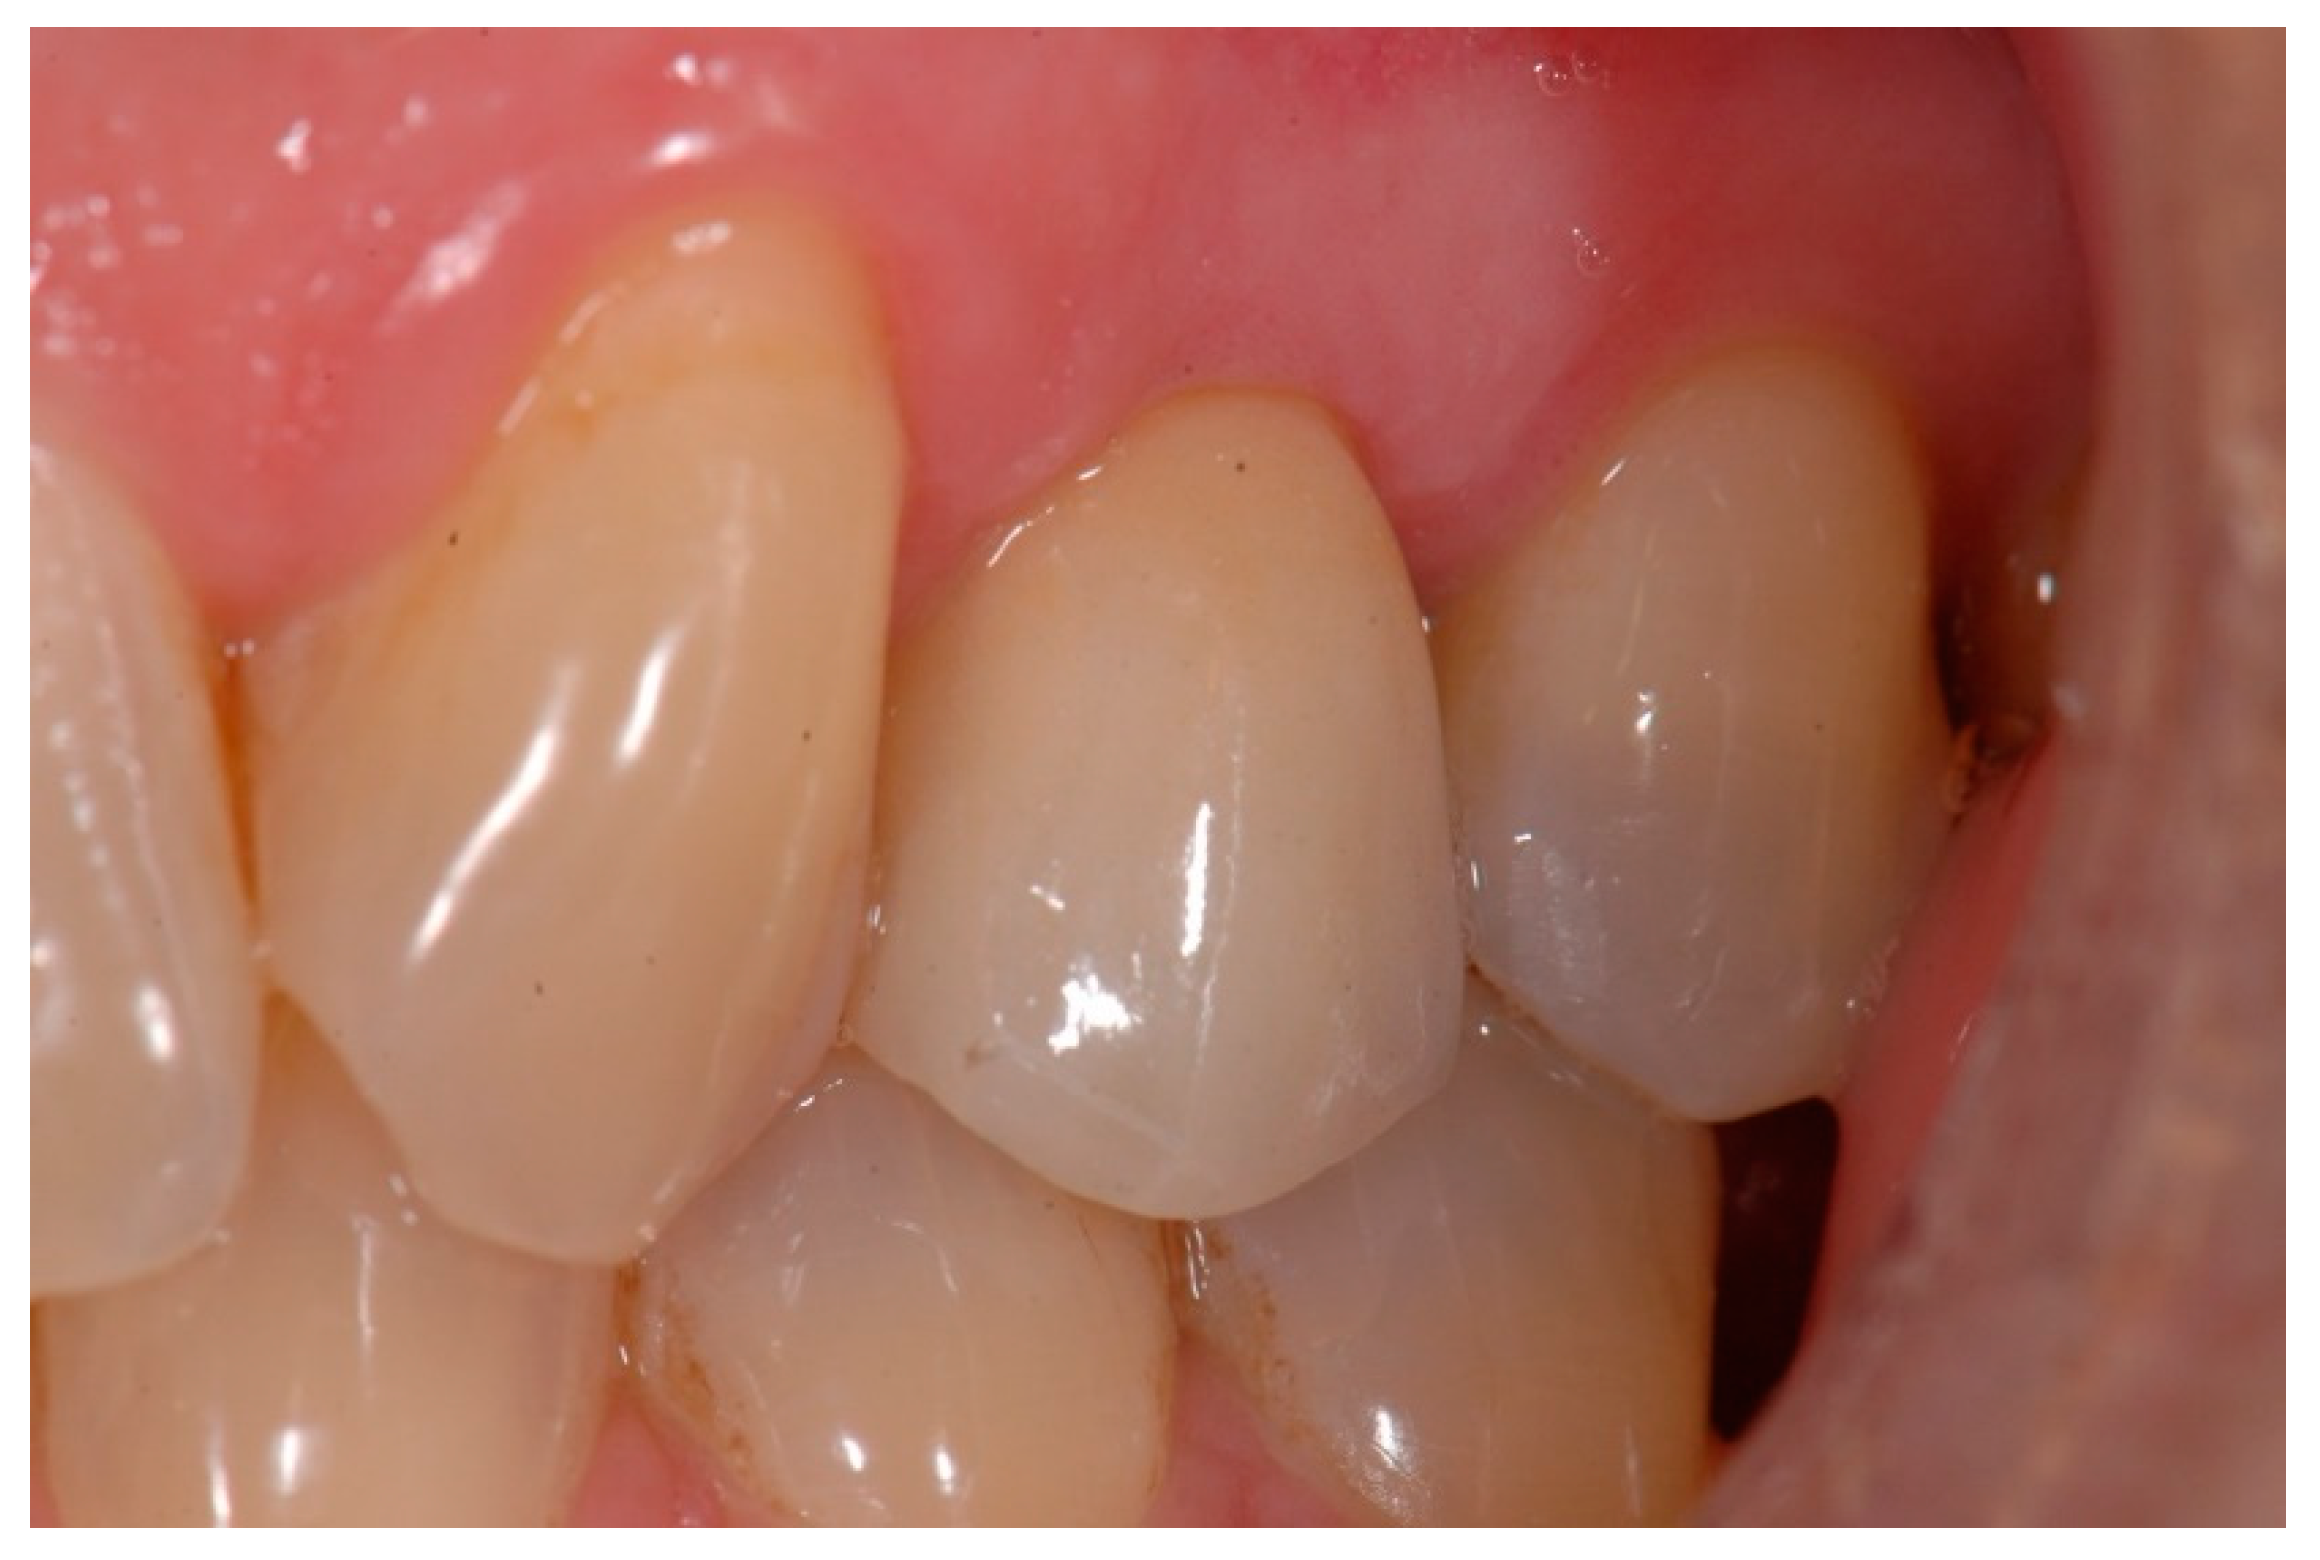

The temporary crown was placed in infraocclusion, ascertaining the absence of occlusal contacts in maximum intercuspidation and during lateral mandibular movements. The gingival implant contours were further adapted by chair-side modifying of the temporary crown. Three months after implant placement, definitive impressions were made using conventional manufacture impression copings. An acrylic try-in was tested and, after laboratory finishing and personalizing, a monolithic zirconia crown was finally cemented using an elastomeric resin cement (Premier® Implant Cement™, Plymouth, MA, USA). Excess cement was carefully removed. Annual follow-up appointments were then scheduled to perform the clinical and radiographic measurements. Figure 5 and Figure 6 illustrate a definitive ceramic nonmetal restoration and the corresponding intraoral X-ray image, respectively, after three years and three months of follow-up.

Figure 5. Definitive ceramic restoration (at 3 years and 3 months of follow-up).